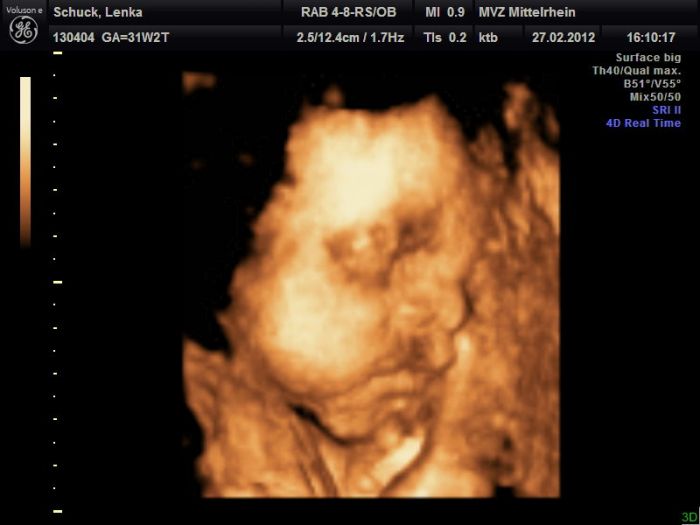

Tak dnes to vyšlo :)) Sice ne úplně dokonale, ale byl to poslední pokus, tak lepší než nic :))) Malej už je holt moc velkej...

Leno,moc hezký fotečky,je vidět,že u je mu tam už těsno.Jinak Maruško už mám13 kg nahoře.

Lenulko ten je krásnej